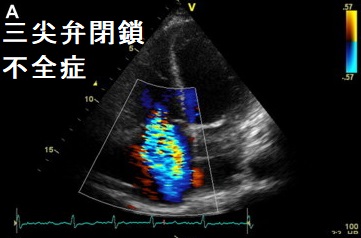

甲状腺機能亢進症/バセドウ病による高拍出量性右心不全では三尖弁輪が拡大して三尖弁が閉じなくなり、三尖弁閉鎖不全症に至る場合があります。治療により甲状腺機能が正常化すれば、右心不全も三尖逆流も消失する可能性があります(Indian Heart J. 2012 Nov-Dec;64(6):600-2.)(Tex Heart Inst J. 2005;32(2):244-5.)。

逆に三尖弁閉鎖不全症では甲状腺機能亢進症/バセドウ病が疑われます。